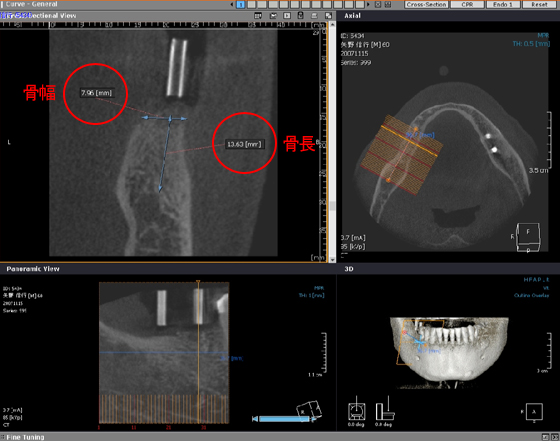

CT画像(3次元)

下顎(下アゴ)欠損部インプラント埋入手術前のCT断面画像です。

骨幅と骨長を正確に測定出来、正確なインプラントサイズを術前に決定しますので

より安全、安心な手術が可能となりました。